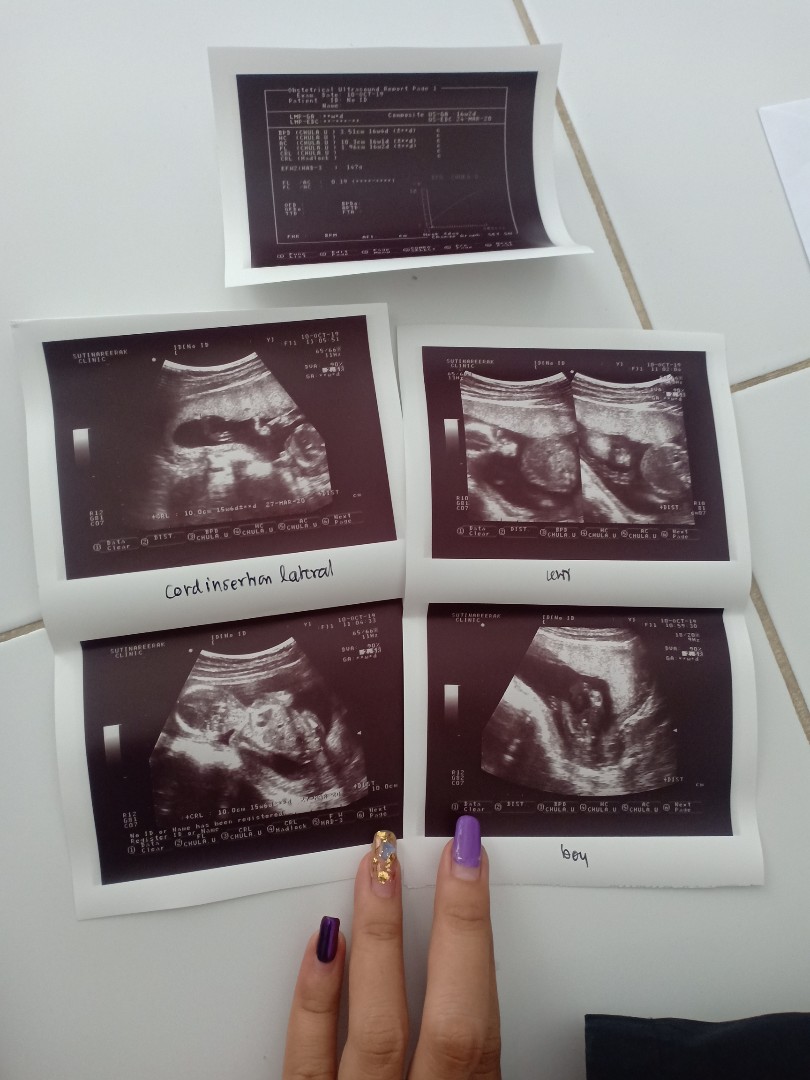

ใบซาวด์

ขอดูใบซาวด์แม่เพศ ชาย หญิง หน่อยค่ะ